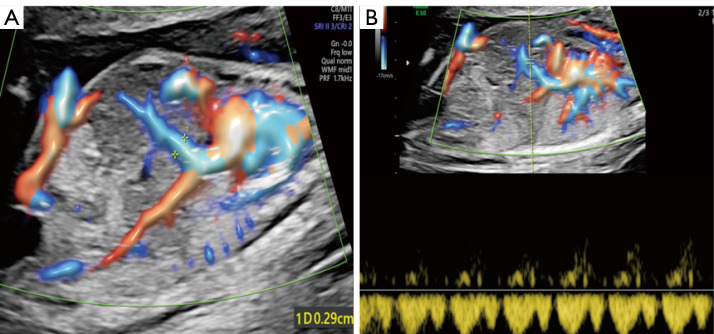

Prenatal diagnosis of abdominal aorta-umbilical vein fistula using high-definition flow render mode and spatiotemporal image correlation.

应用高清血流渲染模式和时空图像相关技术产前诊断腹主动脉-脐静脉瘘。